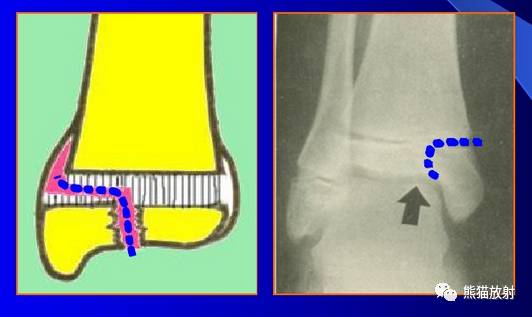

Salter-Harris IV型:骨折累及骺板、干骺端及骨骺,属于关节内骨折。

(上图)胫骨远端骺板变窄,同时可见并发的跟骨骨折。

第四型(Ⅳ型) 骨骺和干骺端骨折。该型也较多见,仅次于第二型,占30.2%;骨折线呈斜形贯穿骨骺、骺板及干骺端,由于骨折线同过生长板全层,所以容易引起生长发育障碍和关节畸形,多见者为鱼尾状畸形。此型多见于10岁以下小儿的肱骨外髁及年龄较大儿童的胫骨远端,此型必须切开复位及内固定。